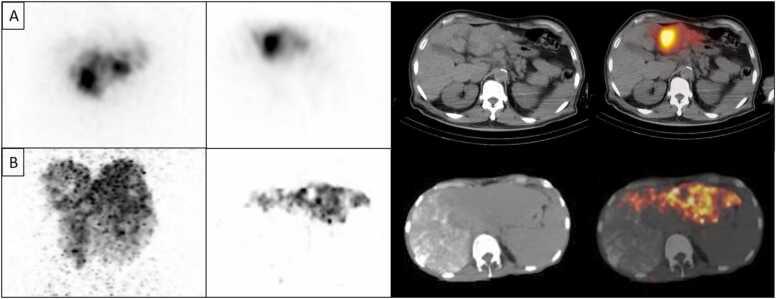

As new molecular tracers are identified to target specific receptors, tissue, and tumor types, opportunities arise for the development of both diagnostic tracers and their therapeutic counterparts, termed "theranostics." While diagnostic tracers utilize positron emitters or gamma-emitting radionuclides, their theranostic counterparts are typically bound to beta and alpha emitters, which can deliver specific and localized radiation to targets with minimal collateral damage to uninvolved surrounding structures. This is an exciting time in molecular imaging and therapy and a step towards personalized and precise medicine in which patients who were either without treatment options or not candidates for other therapies now have expanded options, with tangible data showing improved outcomes. This manuscript explores the current state of theranostics, providing background, treatment specifics, and toxicities, and discusses future potential trends.

随着新的分子示踪剂被确定用于靶向特定受体、组织和肿瘤类型,开发诊断示踪剂及其治疗对应物(即“治疗诊断剂”)的机会应运而生。诊断示踪剂利用正电子发射体或γ发射放射性核素,而它们的治疗诊断对应物通常与β和α发射体结合,这可以将特定的局部辐射传递到靶点,同时对未受影响的周围结构造成最小的附带损伤。这是分子成像和治疗领域令人兴奋的时期,也是迈向个性化精准医学的一步,在这种医学模式下,那些原本没有治疗选择或不适合其他疗法的患者现在有了更多选择,切实的数据表明治疗效果有所改善。本文探讨了治疗诊断学的现状,提供了背景、治疗细节和毒性,并讨论了未来的潜在趋势。